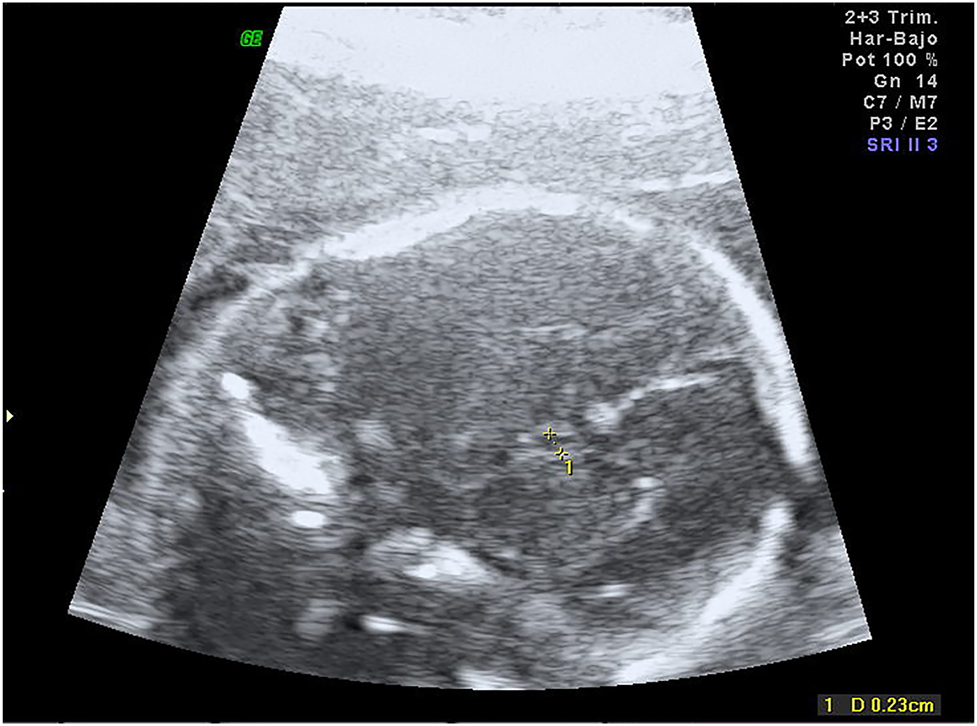

At 30–32 weeks fetal growth remained normal and asymmetric ventriculomegaly developed, the right ventricle posterior horn reached 14 mm and there were signs of germinal matrix hemorrhage along with a secondary periventricular cyst (Figure 2, Supplemental Material, Videos 1 and 2). There was periventricular echogenicity and a complicated periventricular cyst. Medium cerebral artery Doppler showed no signs of anemia. Thrombophilia, infectious diseases screening (toxoplasmosis, parvovirus, cytomegalovirus, listeria), and antiplatelet antibodies studies were negative. CGH Array demonstrated a microdeletion in the short arm of chromosome 16, 16p11.2 (28682192_29076269)x1.

Transvaginal ultrasound at week 32 showing asymmetric ventriculomegaly and periventricular cyst.